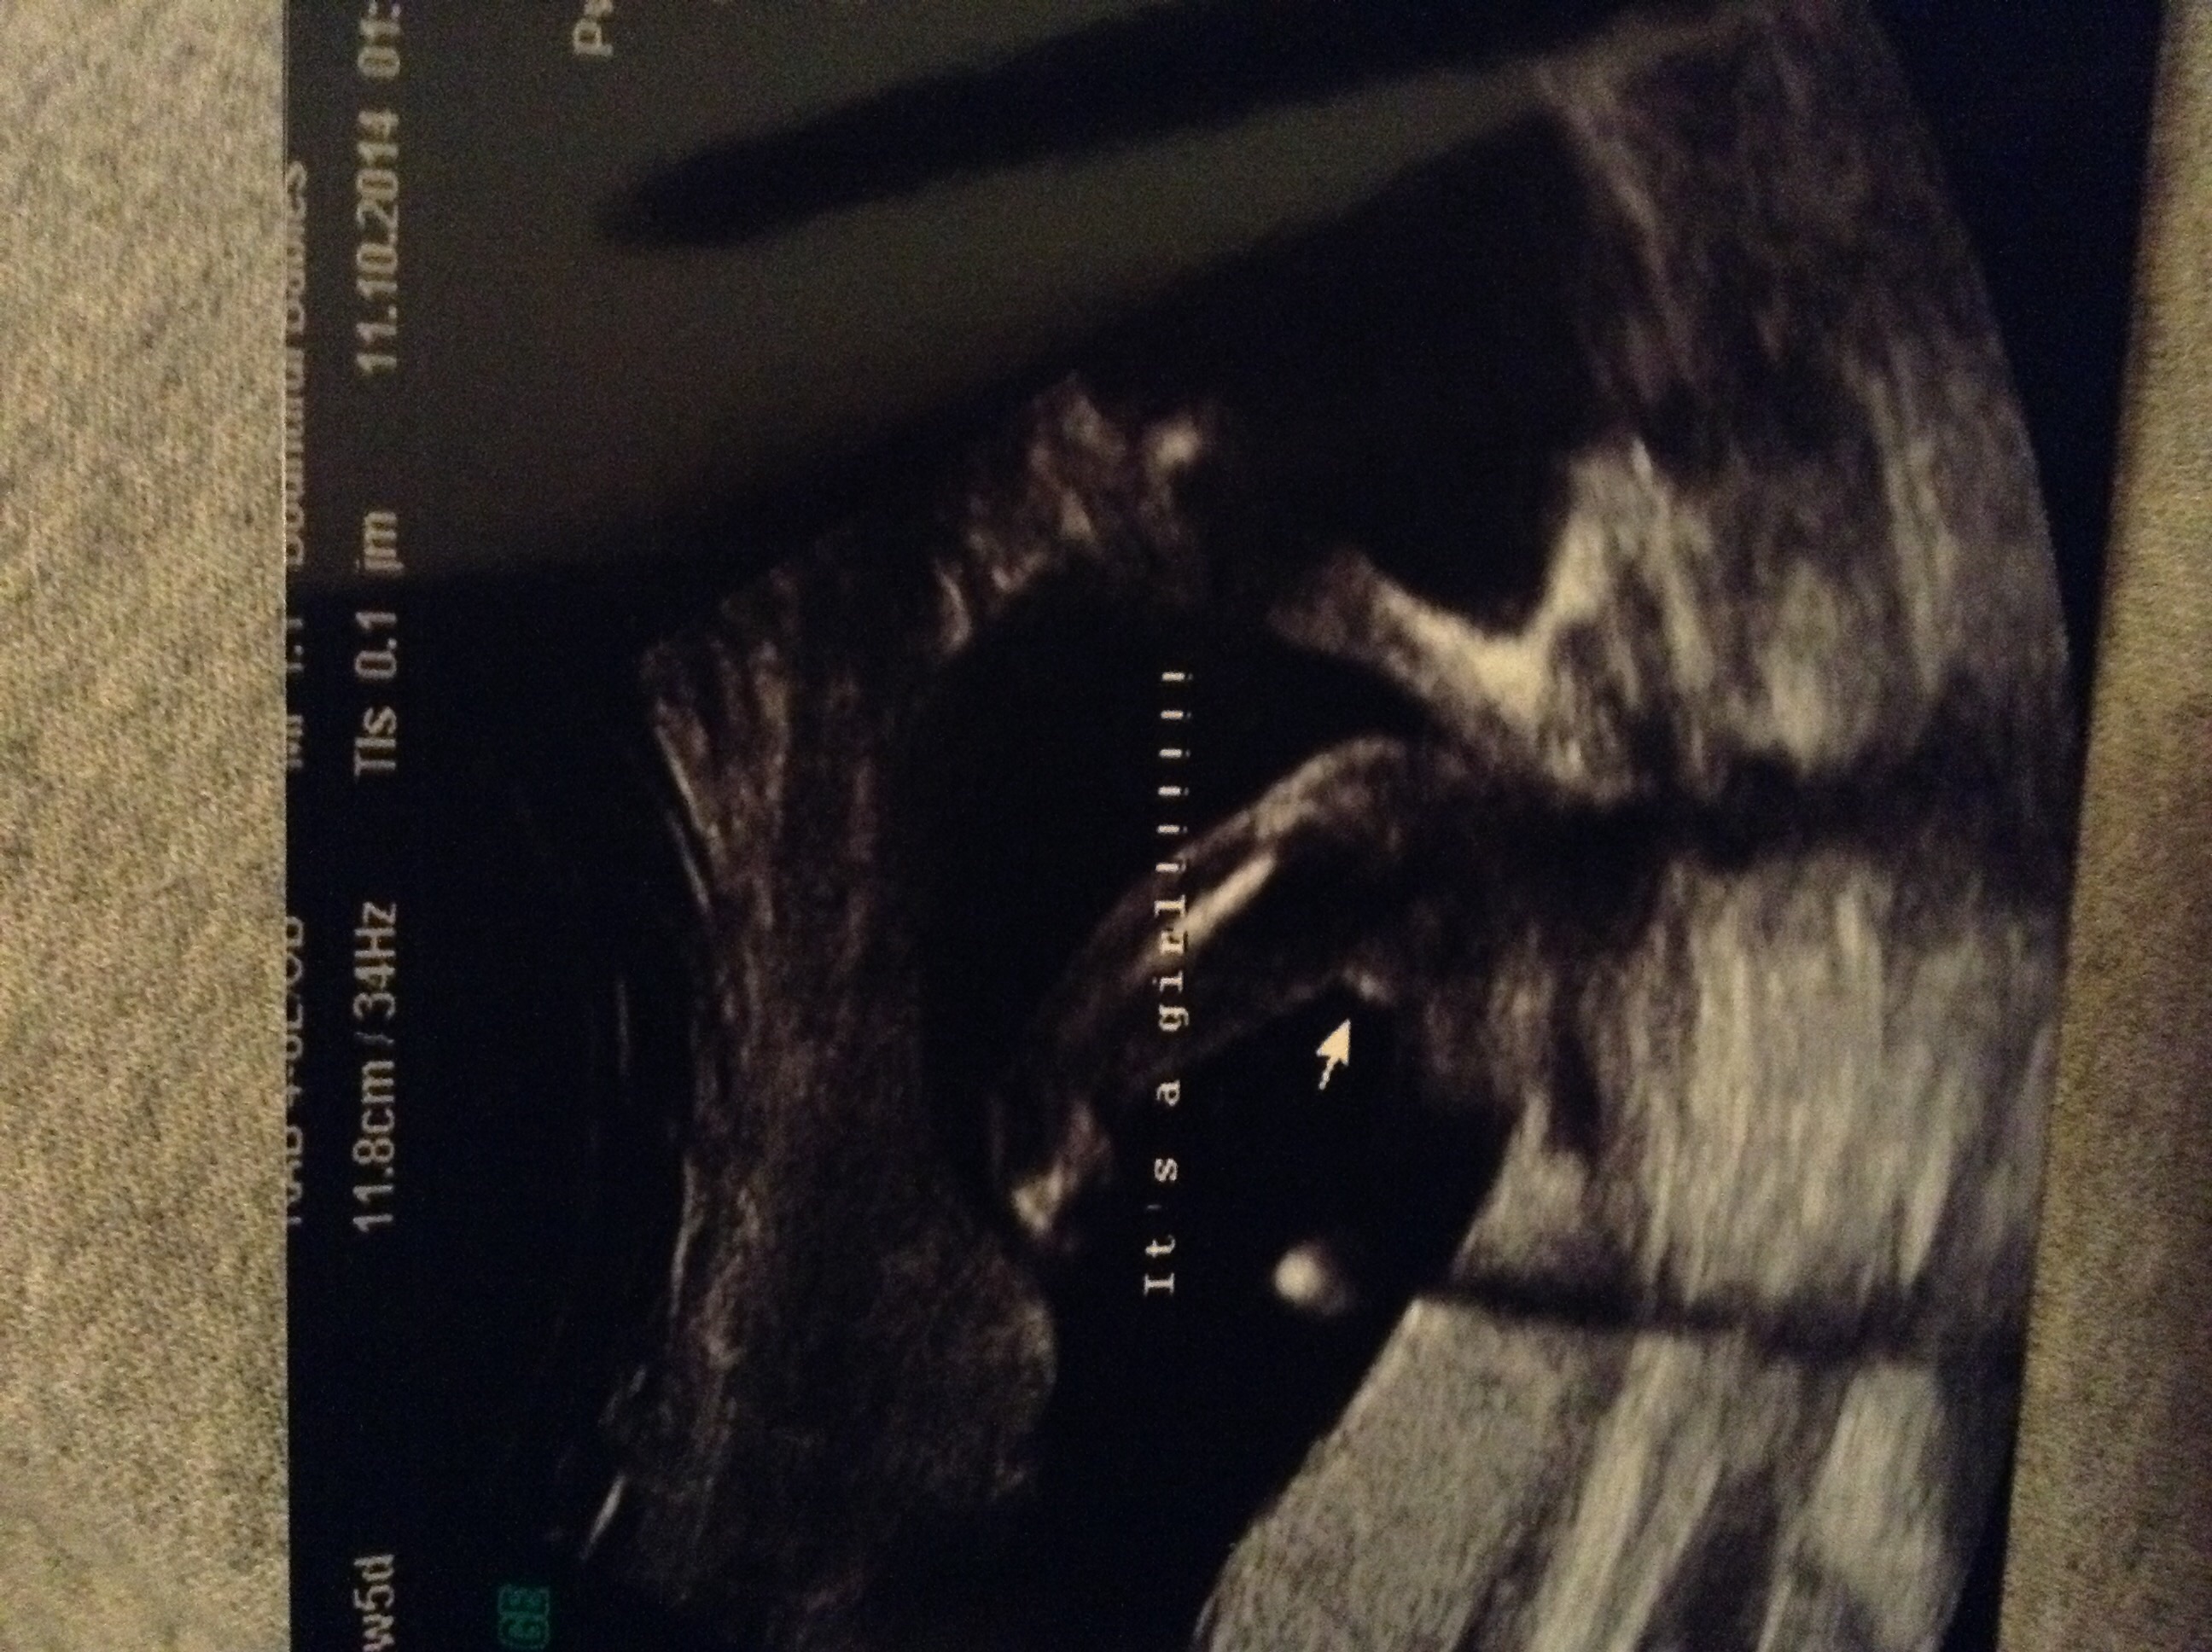

Measuring 12w 5d but only 11w 5d.